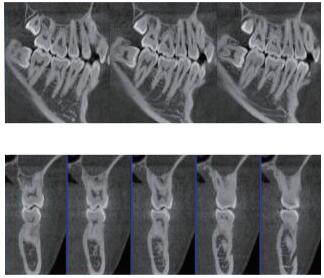

三維重建任意斷層

專有三維重建算法,可提供任意位置高清斷層影像。

多平面組合重建

可同時(shí)觀察軸向面、冠狀面和矢狀面圖像,方便臨床診斷。

口腔CBCT是一種新型的成像技術(shù),可應(yīng)用范圍包括多生牙、根充檢查,牙體牙髓及牙周檢查,種植術(shù)前診斷與設(shè)計(jì)等。如果您想采購普愛醫(yī)療的口腔CBCT,歡迎聯(lián)系我們